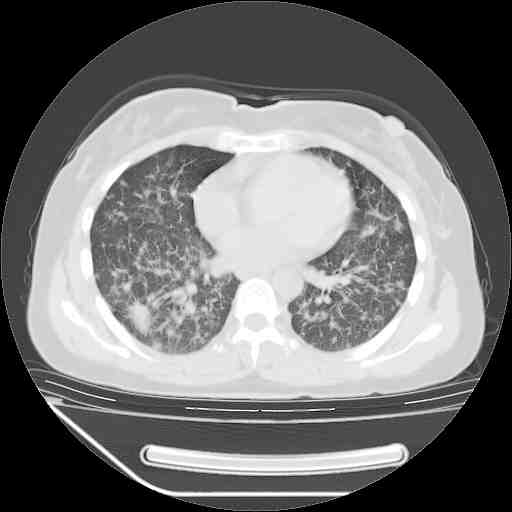

f50,肺ca治疗后,做过穿刺,确诊是肺ca,大家看看这是去年12月做的

考虑  腺癌肺内转移,治疗较前病灶缩小、减少

支持肺癌并肺内淋巴管转移,

肺癌并肺内转移,这种疾病治疗后在影像上看略有好转,不是很显著,但是肿瘤治疗效果影像只是一方面。

支持肺癌并肺内淋巴管炎,  原发灶小了,但转移较前片明显了.

支气管血管束粗而乱,考虑肺癌肺内淋巴管转移,右侧乳房第一二层软组织成份较左侧多,不会有问题吧?

支持右肺下叶周围型肺癌并肺内淋巴管炎,  原发灶小了,但转移较前片明显了.。

标准的细支气管肺泡癌呀!治疗后病情有所控制,也没治愈的迹象!